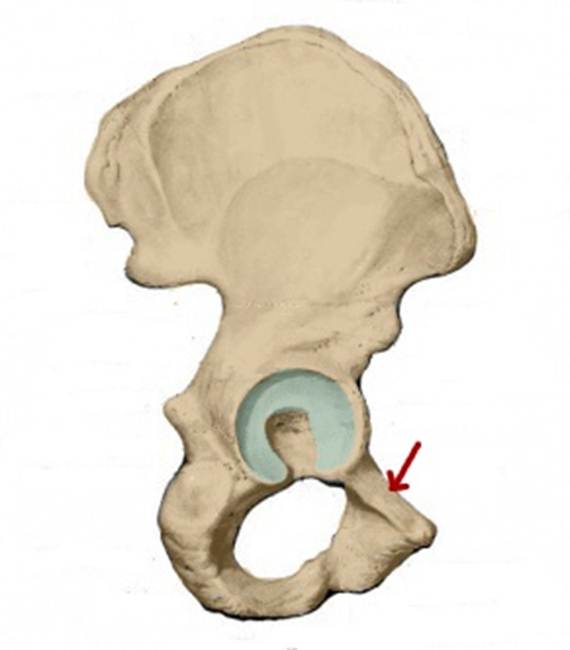

I:

S: Стрелка указывает на os pubis (латинский язык).

I:

S: Стрелка указывает на os ilium (латинский язык).

I:

S: Стрелка указывает на os ischii (латинский язык).

I:

S: Стрелка указывает на ramus superior ossis pubis

I:

S: Стрелка указывает на ramus inferior ossis pubis

I:

S: Стрелка указывает на ramus ossis ischii

S: Стрелка указывает на tuber ischiadicum (латинский язык).

S: Стрелка указывает на foramen obturatum (латинский язык).

S: Стрелка указывает на facies lunata (латинский язык).

S: Стрелка указывает на incisura ischiadica minor

S: Стрелка указывает на incisura ischiadica major

S: Стрелка указывает на incisura acetabuli

S: Стрелка указывает на spina iliaca anterior superior